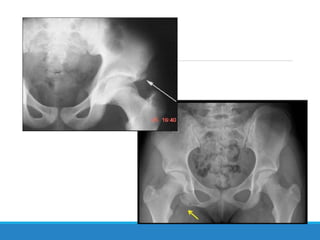

Este documento describe las fracturas de pelvis, incluyendo su etiología, mecanismos, clasificación y tratamientos. Las fracturas de pelvis se clasifican según el sistema de clasificación de Tile, que categoriza las fracturas como Tipo A, B o C dependiendo de su estabilidad y ubicación. El tratamiento depende de la clasificación Tile, con reposo para el Tipo A, estabilización del anillo anterior para el Tipo B, y estabilización anterior y posterior para el Tipo C.